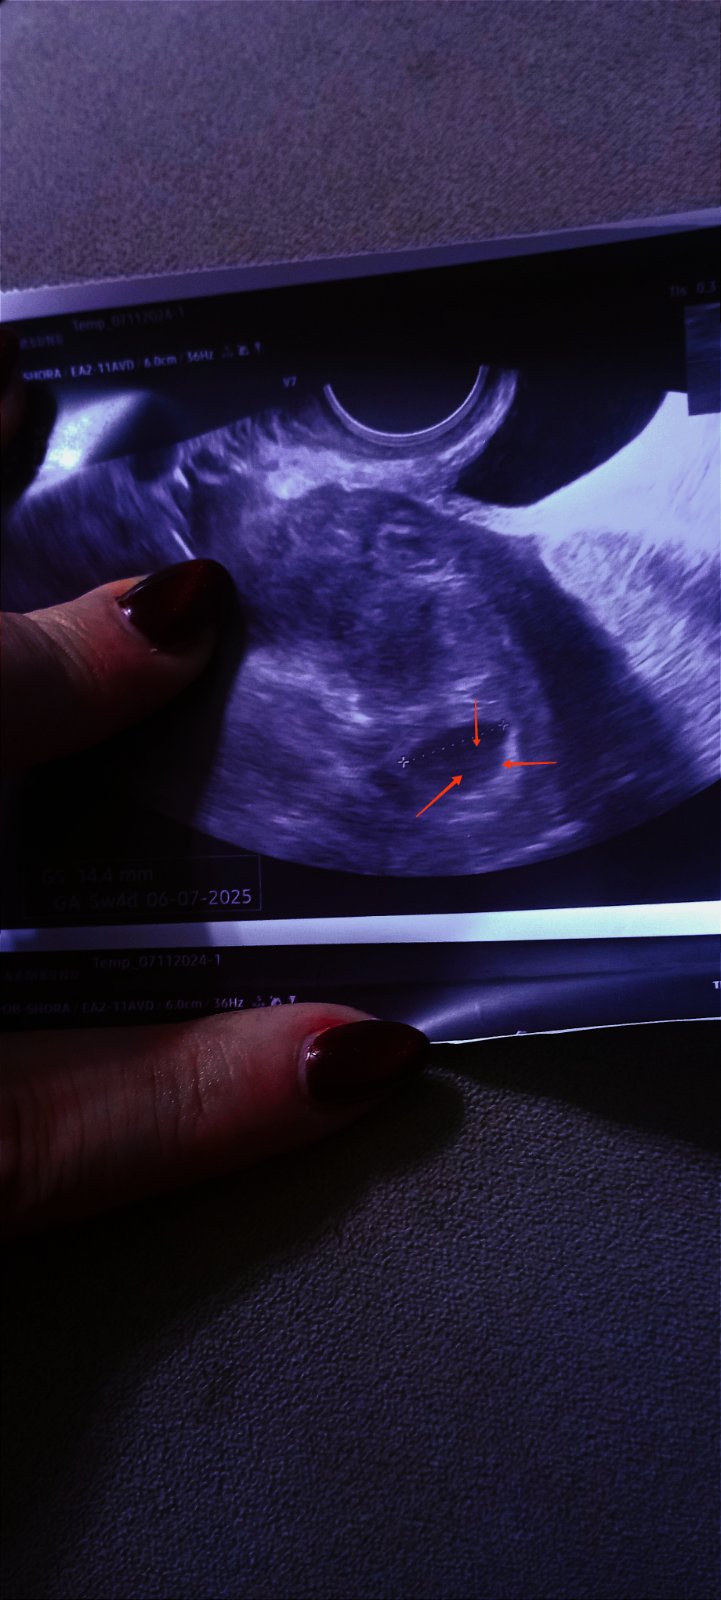

Prázdný gestační váček: Co znamená nález na ultrazvuku?

No uvidíme příští čtvrtek. Opravdu se mi zdálo po zatmaveni, že vidím jakýsi už kroužek. On to teda neztmavoval na utz. Ale jsem nervózní.

Holky, tak už tam je 🙂 plod 3 mm, srdeční akce pomalinku naskakuje 🥰❤️ 6+1 TT, ale podle utz o malinko menší. Ovu byla až 17 DC, to vím.